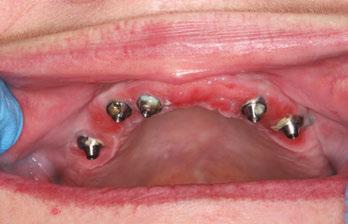

Case report

A 49-year-old female patient presented with the chief complaint of her inabil ity to wear her current full maxillary and mandibular dentures due to a significant gagging reflex, indicating the dentures were delivered 2 years previously. She also expressed dissatisfaction with the current esthetics of the prosthesis and her smile. The patient’s general dentist had referred her for an implant consul tation. Her medical history was reviewed, and no significant health issues were disclosed.

A CBCT scan was taken and panoramic views of the maxilla and mandible evaluated (Figure 3). Bilateral pneumatization of the maxillary sinus was noted, but adequate bone height was present between the premolars for implant placement to support an All-on-X hybrid prosthesis. In the mandibular arch, sufficient height was available between the mental foramen bilaterally and over the inferior alveolar nerve for implant placement to also sup port an All-on-X fixed hybrid prosthesis. A discussion was held with the patient that implants could be placed in both arches that would allow restoration with fixed prosthetics. Should sufficient insertion torque be achieved at the time of implant placement, a screw-retained hybrid provisional prosthesis would be placed and worn for several months during healing after which a final prosthesis would be fabricated. The patient would also be able to do a “trial-run” of the esthetics with the provisional prosthesis, with any requested modifications made when the final prosthesis was designed and fabricated. The treatment plan included six implants in each arch to support the planned hybrid prosthe ses. The patient was informed that reduction of the crestal bone would be required to achieve a flat ridge for adaptation of the prosthesis to the ridge as well as to provide adequate interarch space for the final prosthesis. The patient accepted the treatment plan. An intraoral scan of the arches was performed with Medit i500 (Medit Corp, Seoul, Korea) as well as the current complete arch maxillary and mandibular dentures (Figure 4). The patient was dismissed and scheduled for the surgical appointment.

The patient presented for surgery, and the consent form was reviewed and signed. IV sedation was initiated, and local anes thetic (2% Lidocaine with 1:100,000 epi) was administered in both arches. A crestal incision was made in the maxillary arch midcrest, and a full thickness flap was elevated to expose the buccal and palatal aspects of the ridge. Evaluation of the osseous ridge noted it was fairly flat, and reduction was deemed to be not necessary. The surgical guide was inserted and utilized to guide the location of the osteotomies. ULT implants were placed at the six planned sites: No. 3 (3.75 mm x 13 mm), No. 6 (3.75 mm x 10 mm), No. 8 (3.75 mm x 10 mm), No. 9 (3.75 mm x 11.5 mm), No. 11 (3.75 mm x 10 mm) and No. 14 (3.75 mm x 13 mm). Insertion torque of greater than 40 Ncm was achievable at five of the sites with site No. 10 being less than 30 Ncm and insuf ficient to support an immediate load. As sufficient A-P distance and adequate insertion torque was present utilizing the five other maxillary implants, it was decided to place an immediate provi sional hybrid prosthesis. Multi-unit abutments (MUAs) with the following angulations were placed: (No. 3 = 30 degrees, No. 6= 17 degrees, No. 8= 0 degrees, 11 = 17 degrees, and No. 14 = 30 degrees). The soft tissue was repositioned around the MUAs, and primary closure was achieved utilizing a continuous polylactic acid (PLA) suture.

A scalpel was then utilized to create a crestal incision in the mandible from the approximate first molar on the right to the approximate first molar on the left, and a full thickness flap was ele vated with identification of the mental nerve and its foramen bilaterally. As with the maxillary arch, the mandibular crestal bone was fairly flat, and ridge reduction was not needed. The surgical guide was inserted in the mandible and utilized to guide the location of the osteotomies. ULT implants were placed at six sites as: No. 20 (3.75 mm x 10mm), No. 22 (3.75 mm x 10m m), No. 24 (3.75 mm x 11.5 mm), No. 25 (3.75 mm x11.5 mm), No. 27 (3.75 mm x 10 mm) and No. 30 (3.75 mm x 10 mm). Insertion torque of greater than 40 Ncm was achievable at all of the sites. As sufficient adequate insertion torque was present, placement of an immediate provisional hybrid prosthesis was planned. MUAs with the following angulations were placed (No. 20 = 30 degrees, No. 22 = 0 degrees, No. 24 = 0 degrees, No. 25 = 0 degrees, No 27 = 0 degrees, and No. 30 = 0 degrees). The soft tissue was repositioned around the MUAs, and white protective caps were placed onto the MUAs. Primary closure was achieved, and a continuous PLA suture placed. The patients’ dentures were relieved to seat over the white caps, and a reline impression was taken with the two arches in occlusion to allow use of the current vertical dimension of occlusion (VDO) in the planned fabrication of the provisional hybrid restorations. The patient was dismissed and scheduled for postoperative check and suture removal in 2 weeks.